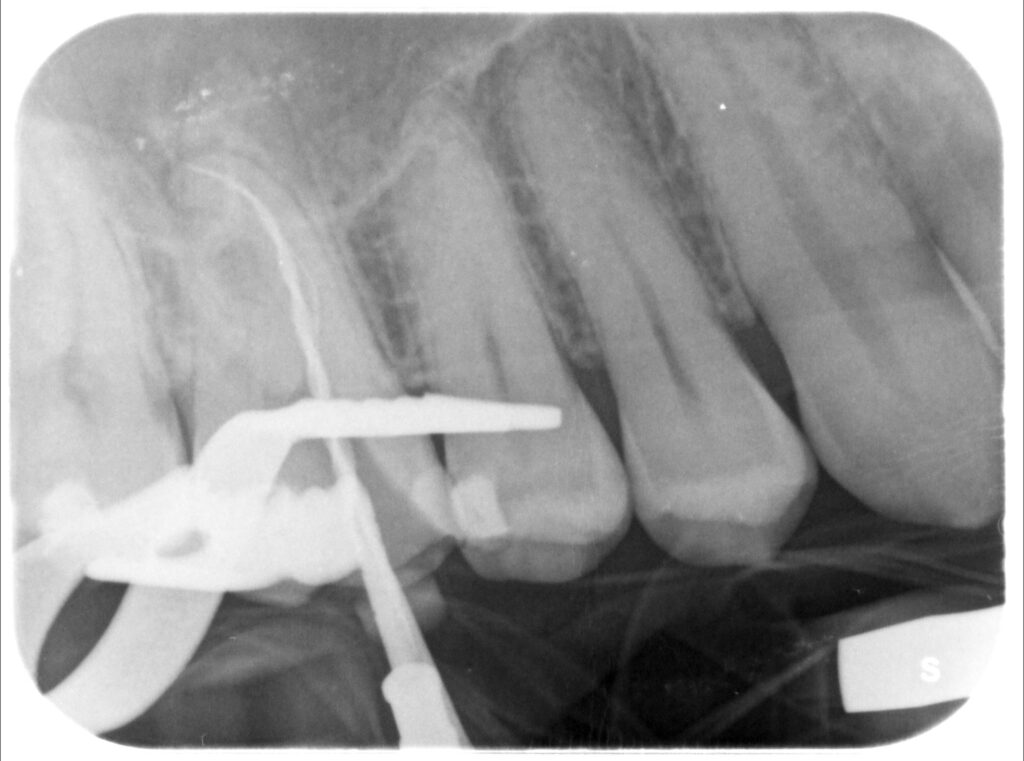

Caso clinico – trattamento ortogrado 1° molare superiore con lesione